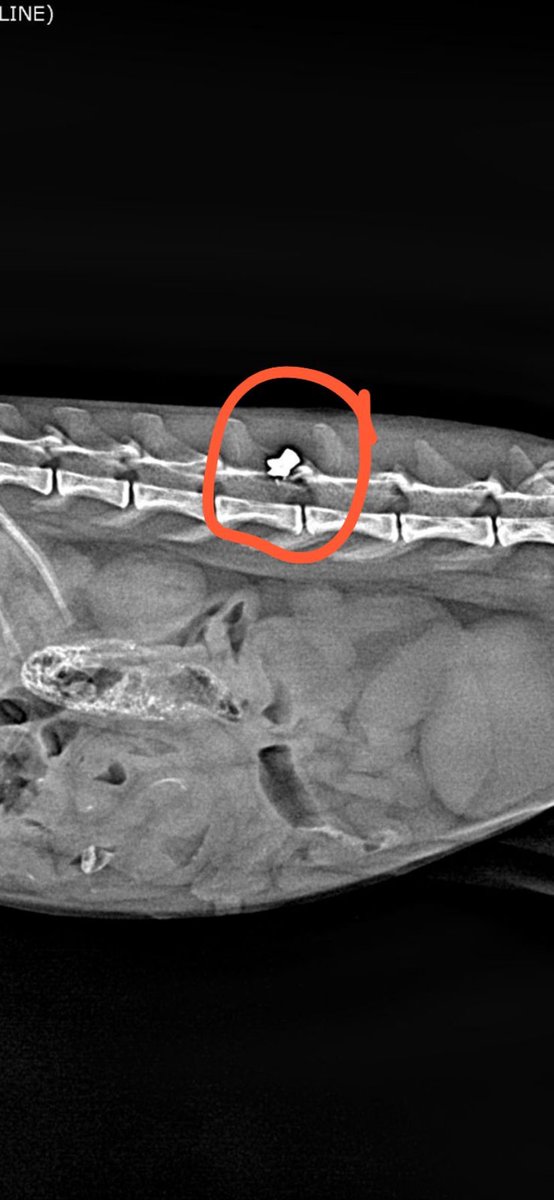

هذا القط سبق اعلنت عنه وتم الإنقاذ الحمد لله

والقط الآن تحت العلاج وسيتم تعقيمه

والا بيرجع الشارع 💔

ذكر عمره من سنين إلى ثلاث سنوات نحتاج له متبني عاجل بالرياض مايقدر القط يرجع للشارع ،، سبب حالته السيئة والجروح من قطط الشارع ( اقدر أوصل القط لمنزل المتبني ) للتواصل 0564840318